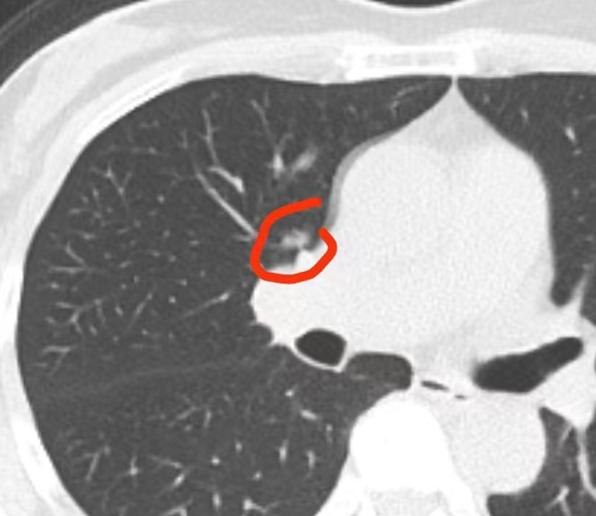

医生最开心、最有成就感的时候,就是能真正帮到患者、为患者解决病痛的那一刻。 刚刚我就完成了一台这样的手术,患者是一位年轻女性,检查时发现了一个磨玻璃结节。这个结节密度较高,CT值约为负三四百,但体积很小,只有8毫米。 虽然观察期间发现结节有缓慢变化,但它的位置非常不好——长在肺根上。 我跟患者打了个比方:这个结节就像长在了大树的树根上,这么小的一个结节,如果因为它就把整棵“大树”(整个肺叶)都切掉,实在是太划不来了。 所以,我特意设计了手术方案,我们称之为“刮皮式”切除。手术时,从肺根部(也就是“树根”部位)像刮皮一样操作,先把供应该区域的几根动脉、静脉(相当于大树的几根主根)断掉,断掉之后再把这部分组织掀起来。 这样一来,就不用切除整个肺叶,只需要将这几根“树根”(动脉静脉)连同部分“树干”(肺组织)从根部掀起来,完成一个肺段切除即可。结节本身很小,这样的切除范围也很小,最大程度保留了患者大部分的肺功能。 虽然这台手术难度很大,也存在一定风险,但做完之后我真的特别开心、特别有成就感。 这样的手术我已经做了几十例,患者的结节都位于血管根部,通过这种“刮起来、翻起来、掀起来”的方式,既能精准切除结节,又能给患者带来巨大的益处,最大程度减少手术对身体的损伤。[作揖][玫瑰]